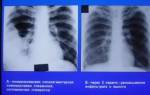

- рентген. Эта процедура назначается в первую очередь при подозрении на пневмонию. Она позволяет определить локализацию воспалительного процесса. На снимке также проявляются патологические изменения в корнях легких;

Грамотный доктор способен определить вялотекущую пневмонию при прослушивании лёгких. Будут слышны звуки от трения плевры и хрипы разного тона. У таких пациентов дыхание обычно жёсткое. Для подтверждения диагноза больной направляется на рентген или МРТ. Эти способы обследования позволяют выявить даже маленькие очаги патологии.

Роль в диагностики этой формы воспаления легких играет не момент начала болезни, а отсутствие положительной динамики при проведении рентгена и наличие повторного обострения в одном и том же месте легкого при правильном лечении и долговременном динамическом наблюдении.